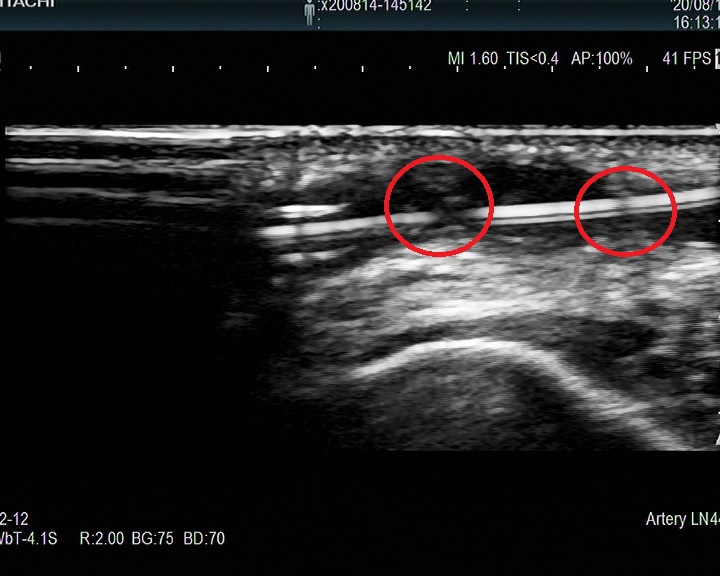

血液透析血管通路的建立与维护:科室拥有血管通路医护团队,设有血管通路专病门诊,多学科协同术前彩色多普勒血管超声检查、术中超声引导以及术后通路超声复查、复杂血管通路及中心静脉的CT血管成像(CTA)和数字减影血管造影(DSA),可开展经皮B超引导下内瘘血管腔内成形术(PTA)、肢体静脉动脉内瘘手术、中心静脉血透导管置入术以及DSA下中心静脉狭窄球囊扩张后建立血透导管等疑难复杂通路的问题。

(3)B超引导下经皮腔内血管成形术(PTA):

图 PTA扩张狭窄的血管

图 超声引导下PTA球囊封堵治疗假性动脉瘤术前后对比